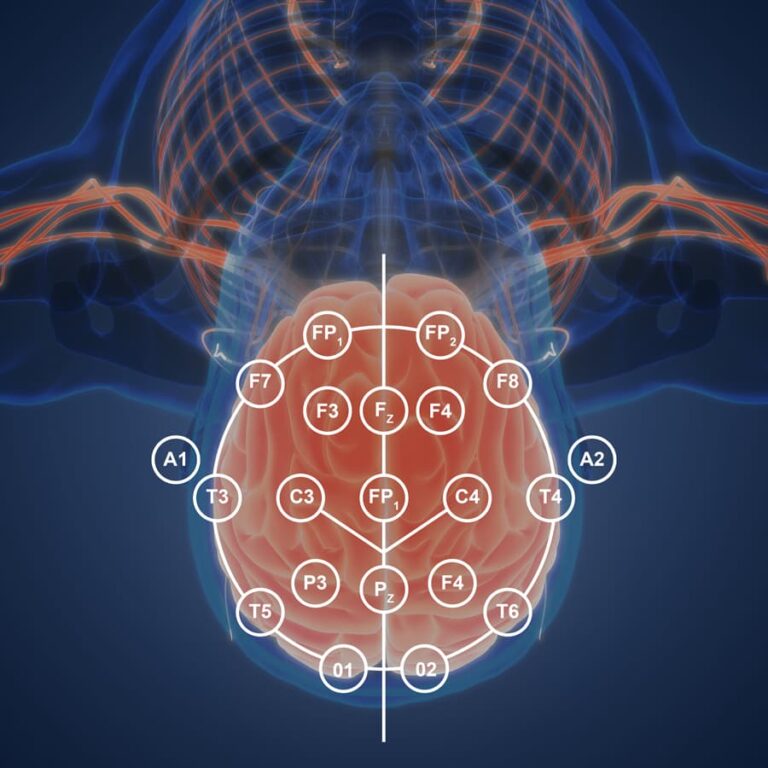

- qEEG recording and interpretation

- Surface and Z score 19 channel feedback utilizing Deymed amp and Neuroguide software

Sensors are placed on the “trainee’s” scalp and ear. Brainwaves are monitored by a computer and goals are set that require the trainee to voluntarily produce more beneficial brain wave patterns. A second linked computer “coaches” the trainee by presenting visual, auditory and tactile representations of the trainee’s brainwave signals in a video game format.

19 channel Z-score LORETA